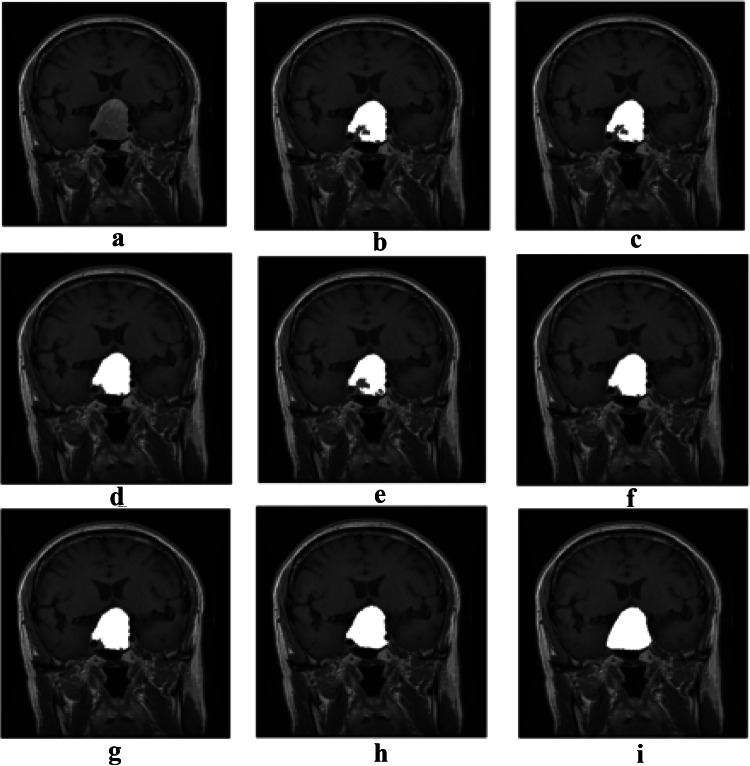

After comparing the results of the mentioned algorithms and evaluating the defined comparison criteria, the PSO algorithm had the best performance among the other algorithms. Nevertheless, to achieve a higher accuracy, it is required to use an algorithm which is able to obtain the edges of the tumor more accurately. The Active contour algorithm can perform very well but it is highly dependent on the initial boundary. Henceforth, the tumor area detected by the PSO algorithm is used as an initial boundary for the Active contour model. Figure 5 shows the results of tumor detection from a MRI brain image using Active contour with an initial boundary obtained by PSO algorithm for both types of tumors. We call this combination as our proposed algorithm. Rows 1 to 3 in Fig. 5 depict the images containing the pituitary tumor, and rows 4 to 6 show the images containing the Meningioma tumor. The results of PSO algorithm and our proposed algorithm for 30 images containing the Meningioma tumor are presented in Table 8. All the evaluation criteria computed for the proposed algorithm, except Precision, have been significantly increased, which shows that the proposed algorithm has a higher ability to obtain tumor edges than the PSO. The high Precision of PSO algorithm is due to the fact that the algorithm has obtained the area inside the tumor, so it has a low FP, and as a result, the Precision has been increased according to its formula. However, since this algorithm has performed poorly in obtaining the edges, the FN is very high which results in a very low Recall and other evaluation criteria. Figure 6 shows the results of tumor detection on MRI brain images containing the Meningioma tumor using different algorithms. Figure 7 shows the same results on MRI brain images containing the Pituitary tumor.

Fig. 5.

Tumor detection results for both types of tumors: a original images, b initial segmentation using PSO algorithm, c tumor area by means of PSO, d the proposed algorithm, and e ground truth

Fig. 7.

The results of tumor detection on a MRI brain image containing the pituitary tumor: a original image, b ABC, c DE, d GA, e HS, f GWO, g PSO, h the proposed algorithm, and i ground truth

Table 9 shows the performance evaluation of the proposed algorithm and PSO for 20 MRI images containing the pituitary tumor.

According to Table 9, the accuracy, Recall, F-score, and Jaccard of the proposed algorithm are much higher than those of the other evolutionary methods, K-means, and Otsu thresholding. As mentioned above, high Precision indicates that most of the resulting area is tumor, but it may not identify many parts of the real tumor. According to the aforementioned reasons for the poor performance of PSO in finding the edges, a high Precision may be obtained by PSO but it cannot reach a high Recall, and ultimately, it performs worse than our proposed algorithm.